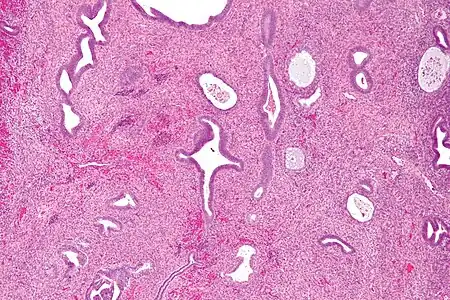

Pathology

Endometrial polyps can be solitary or occur with others.[12] They are round or oval and measure between a few millimeters and several centimeters in diameter.[7][12] They are usually the same red/brown color of the surrounding endometrium although large ones can appear to be a darker red.[7] The polyps consist of dense, fibrous tissue (stroma), blood vessels and glandlike spaces lined with endometrial epithelium.[7] If they are pedunculated, they are attached by a thin stalk (pedicle). If they are sessile, they are connected by a flat base to the uterine wall.[12] Pedunculated polyps are more common than sessile ones.[11]